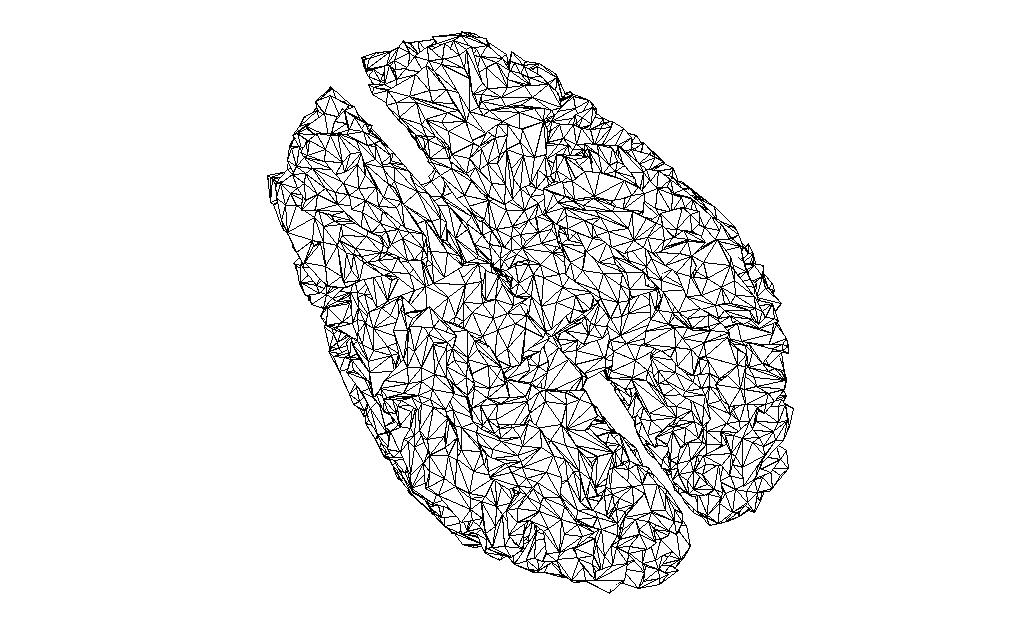

And the source space of the same volume created in FieldTrip, and reduced to the same number of vertices with the MATLAB reducepatch function

bnd2_ft = bnd_ft;

[bnd2_ft.tri, bnd2_ft.pnt]=reducepatch(bnd_ft.tri, bnd_ft.pnt, 16384);

ft_plot_mesh(bnd2_ft);